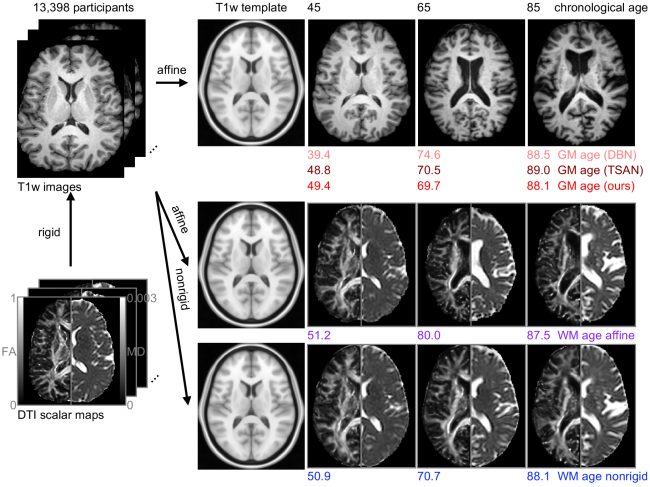

Estimated brain age from magnetic resonance image (MRI) and its deviation from chronological age can provide early insights into potential neurodegenerative diseases, supporting early detection and implementation of prevention strategies to slow disease progression and onset. Diffusion MRI (dMRI), a widely used modality for brain age estimation, presents an opportunity to build an earlier biomarker for neurodegenerative disease prediction because it captures subtle microstructural changes that precede more perceptible macrostructural changes. However, the coexistence of macro- and micro-structural information in dMRI raises the question of whether current dMRI-based brain age estimation models are leveraging the intended microstructural information or if they inadvertently rely on the macrostructural information. To develop a microstructure-specific brain age, we propose a method for brain age identification from dMRI that mitigates the model’s use of macrostructural information by non-rigidly registering all images to a standard template. Imaging data from 13,398 participants across 12 datasets were used for the training and evaluation. We compare our brain age models, trained with and without macrostructural information mitigated, with an architecturally similar T1-weighted (T1w) MRI-based brain age model and two recent, popular, openly available T1w MRI-based brain age models that primarily use macrostructural information. We observe difference between our dMRI-based brain age and T1w MRI-based brain age across stages of neurodegeneration, with dMRI-based brain age being older than T1w MRI-based brain age in participants transitioning from cognitively normal (CN) to mild cognitive impairment (MCI) (p-value = 0.023), but younger in participants already diagnosed with Alzheimer’s disease (AD) (p-value < 0.001). Classifiers using T1w MRI-based brain ages generally outperform those using dMRI-based brain age in classifying CN versus AD participants. Conversely, dMRI-based brain age may offer advantages over T1w MRI-based brain age in predicting the transition from CN to MCI.